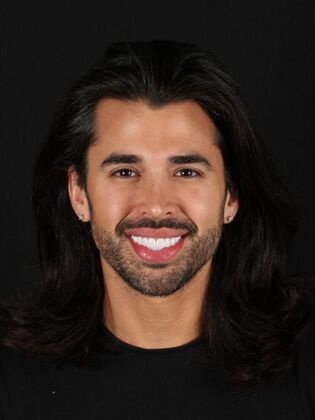

Full Mouth Rehabilitation: Eric

Description

Eric had pre-existing veneers he was wanting to have upgraded and one had recently broken while out of state. Once we consulted, we discovered Eric's bite was destructive leading to frequent headaches, popping & clicking in the jaw joints, and overall jaw fatigue. We discussed upgraded his porcelain restorations and opening his bite in order to correct his TMJ dysfunction. Treatment was completed using TENS and separated into two appointments for the top and two appointments for the bottom arch several weeks apart. Now, Eric is TMJ dysfunction free!